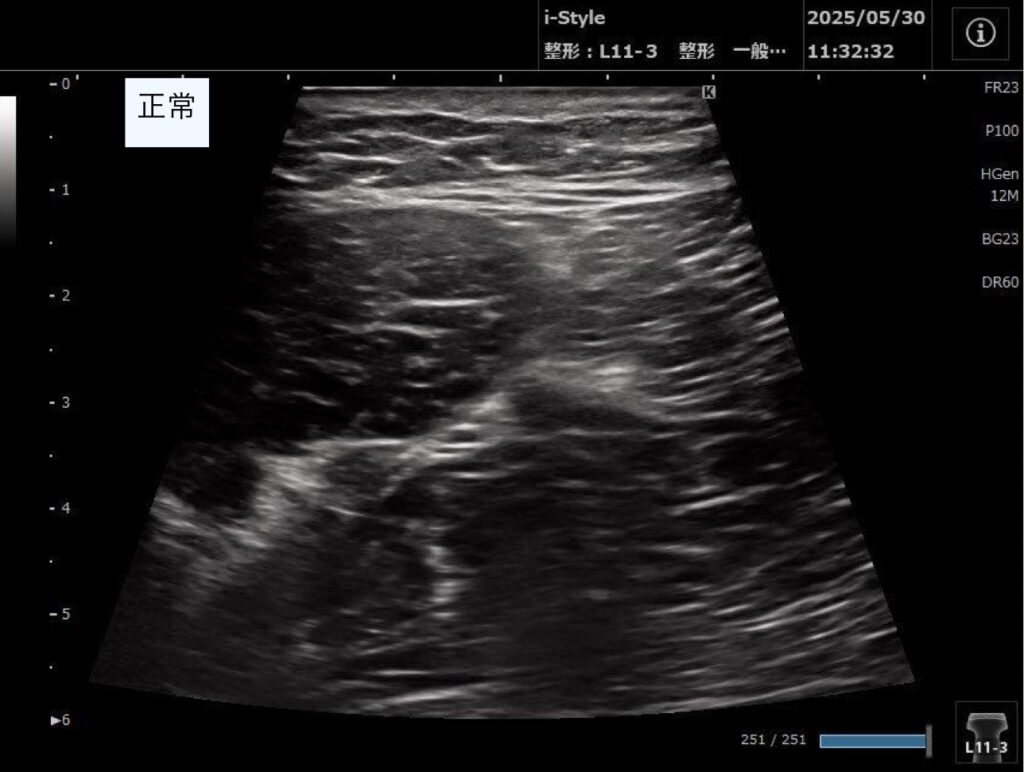

・超音波エコーで観察した結果、ハムストリングの筋が重なっている部分(共同腱)の収縮の低下があり、半腱様筋周囲に血種の低エコー像を認めた。

2回目以降:歩行や日常生活での痛みはさらに改善した。超音波エコーでの観察は毎回行い、血腫の吸収具合を確認し筋肉や神経の癒着を改善していった。

スポーツ復帰のタイミングは痛みのありなしでの判断ではなく、毎回超音波エコーで確認を行い、しっかりと筋収縮が行えることを確認できた、8週間後となった。